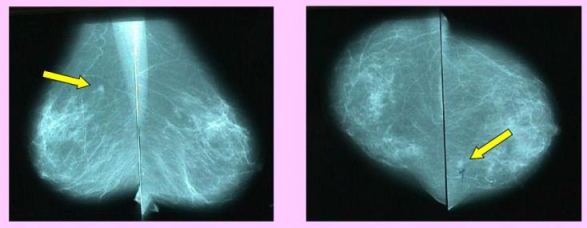

Soustředění vyšetřovacích metod na jednom pracovišti

umožňuje:

- Hodnocení momgramů dvěma lékaři

- Negativní výsledek vyšetření do 3 dnů

- Provedení histologického vyšetření při podezřelém nálezu do 14 dnů od mamografie

- Značení nádorového ložiska nutné k prs zachovávajícím operacím